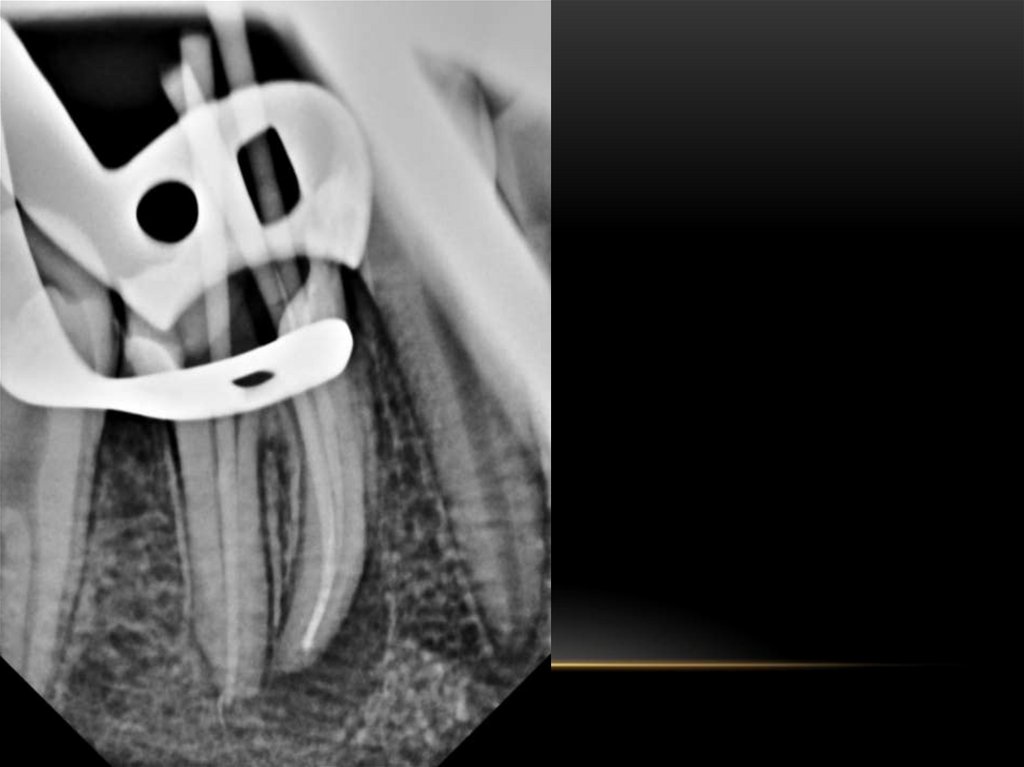

Механическая обработка корневых каналов. Этапы эндодонтического лечения

Принципы препарирования корневых каналов. Алгоритмы эндодонтического лечения

Эндодонтическое лечение зубов. Инструментальная обработка корневых каналов. Лекция 3-4

Механическая обработка корневых каналов